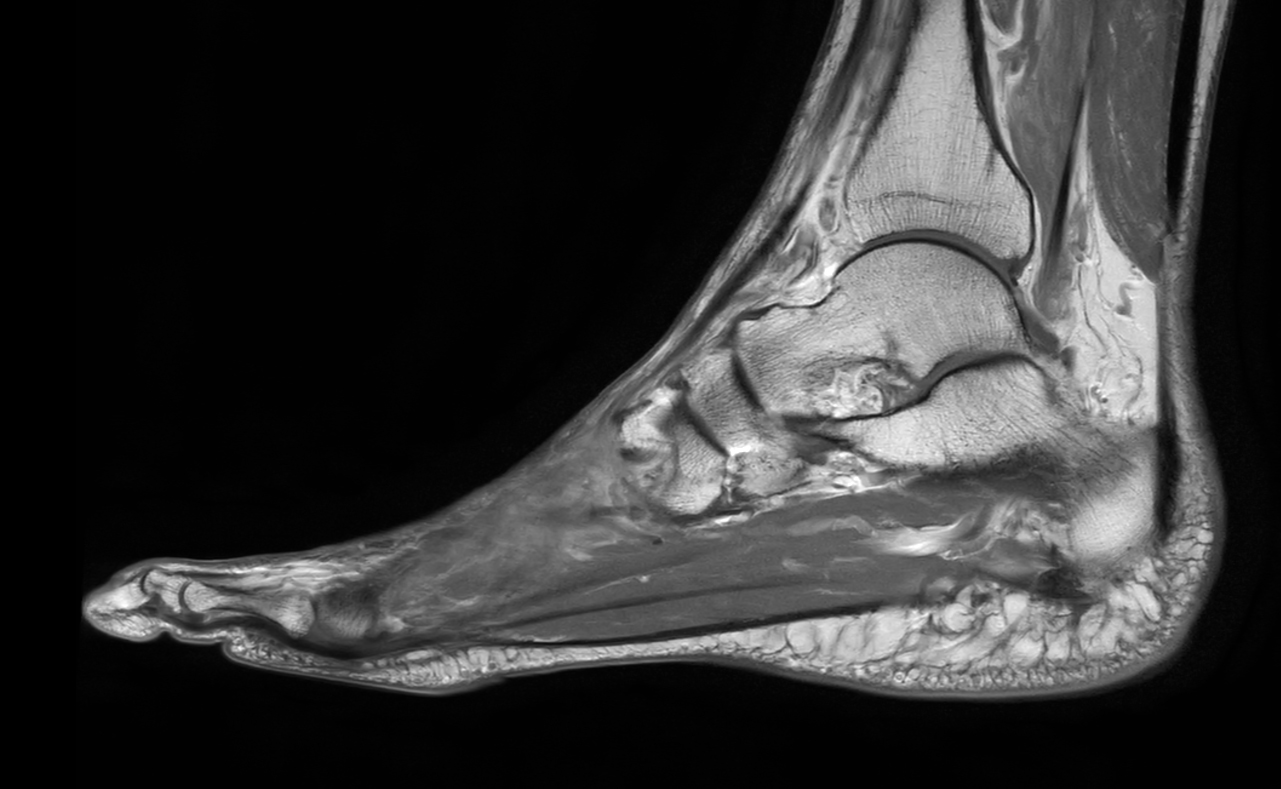

Ankle/Foot imaging post-amputation

Patient with partial amputation of the foot

Sagittal T1w TSE